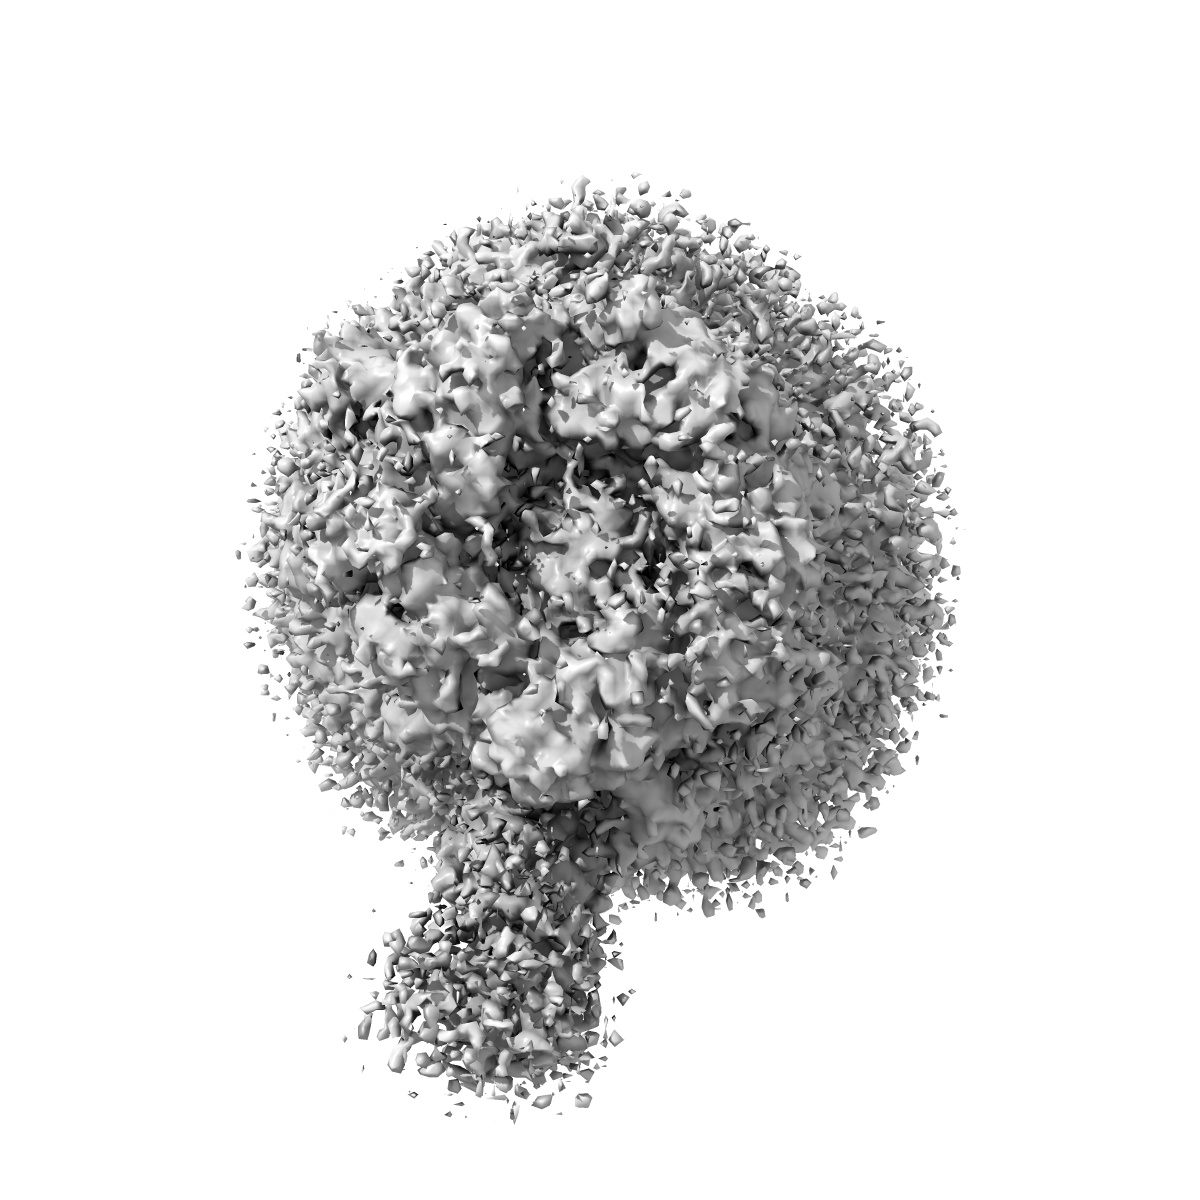

Cryo-EM structure of the full-length alpha1beta3gamma2 GABA(A) receptor in large MSP2N2 nanodisc in complex with GABA in the long-lived symmetric desensitised state

Sample: Cryo-EM structure of the full-length alpha1beta3gamma2 GABA(A) receptor in large MSP2N2 nanodisc in complex with GABA in the long-lived symmetric desensitised state